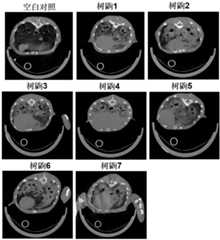

图3是树鼩LPS诱导后micro-CT检测结果图。Figure 3 is a graph showing the results of micro-CT detection in tree shrew after LPS induction.

(15)树鼩micro-CT测定肺部病变:使用平生Super Nova CT(SNC-100)以肺窗和纵膈窗扫描,分析动物肺部病变情况。(15) Determination of lung lesions by micro-CT in tree shrew: The lung and mediastinum windows were scanned with the Super Nova CT (SNC-100) of Lifetime to analyze the lung lesions of animals.

树鼩气管插管200mg/kg的LPS溶液,树鼩肺部损伤面积至少在70%以上(见图3);病理切片显示肺间质轻度至中度弥漫性增宽,轻度至中度水肿,肺间质和肺泡腔内可见明显大量泡沫细胞分布,肺脏可见嗜中性粒细胞浸润,巨噬细胞增多,支气管腔内可见脱落上皮细胞、泡沫细胞及嗜酸性分泌物,肺泡结构消失,肺不张(见图4);树鼩肺水肿情况见表2。The tree shrew was intubated with 200 mg/kg LPS solution, and the lung damage area of the tree shrew was at least 70% (see Figure 3); pathological sections showed mild to moderate diffuse widening of the lung interstitium, mild to moderate Edema, a large number of foam cells can be seen in the pulmonary interstitium and alveolar cavity, neutrophil infiltration in the lungs, increased macrophages, exfoliated epithelial cells, foam cells and eosinophilic secretions can be seen in the bronchial cavity, and the alveolar structure disappears. Atelectasis (see Figure 4); tree shrew pulmonary edema is shown in Table 2.